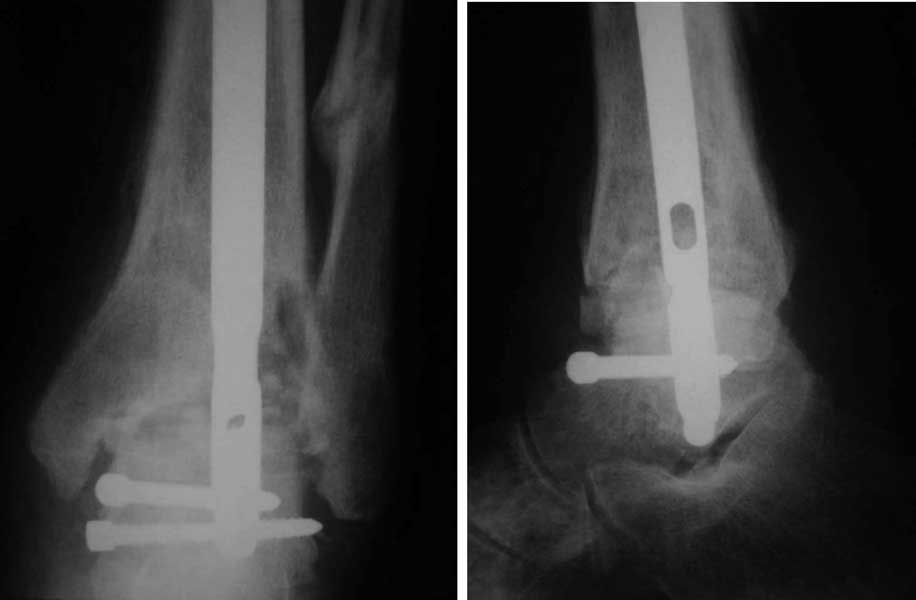

Уважаемый Александр Николаевич! Вот фото рентгенограмм.

Интересный случай. Допускаю, что состояние мягких тканей приемлемое. Цель лечения должна заключаться, как мне кажется, в ликвидации ложного сустава и достижении артродеза голеностопного сустава. Впрочем, это две взаимосвязанные задачи. Мы бы оперировали следующим образом. Остеотомия малоберцовой кости на вершине деформации. Передне-медиальным доступом артротомия голеностопного сустава, резекция суставных поверхностей с отломков большеберцовой и таранной костей, удаление рубцов между отломками дистального эпиметафиза большеберцовой кости, антеградный стержень с дистальным блокированием в таранной кости, костная пластика дефекта спонгиозным костным трансплантатом из крыла (возможно сразу из двух) подвздошной кости. Банальные артродезы голеностопного сустава мы обычно выполняем антеградным блокированным стержнем (см. вложенный файл),

что позволяет сохранить подтаранный сустав, и нагружать ногу сразу после операции.

Артродез штифтом